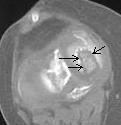

А вот примерно так выглядит это ложе на КТ, пока оно ещё не опустело (ложе в медиальном мыщелке помечено стрелками). Б-нь Кенига.